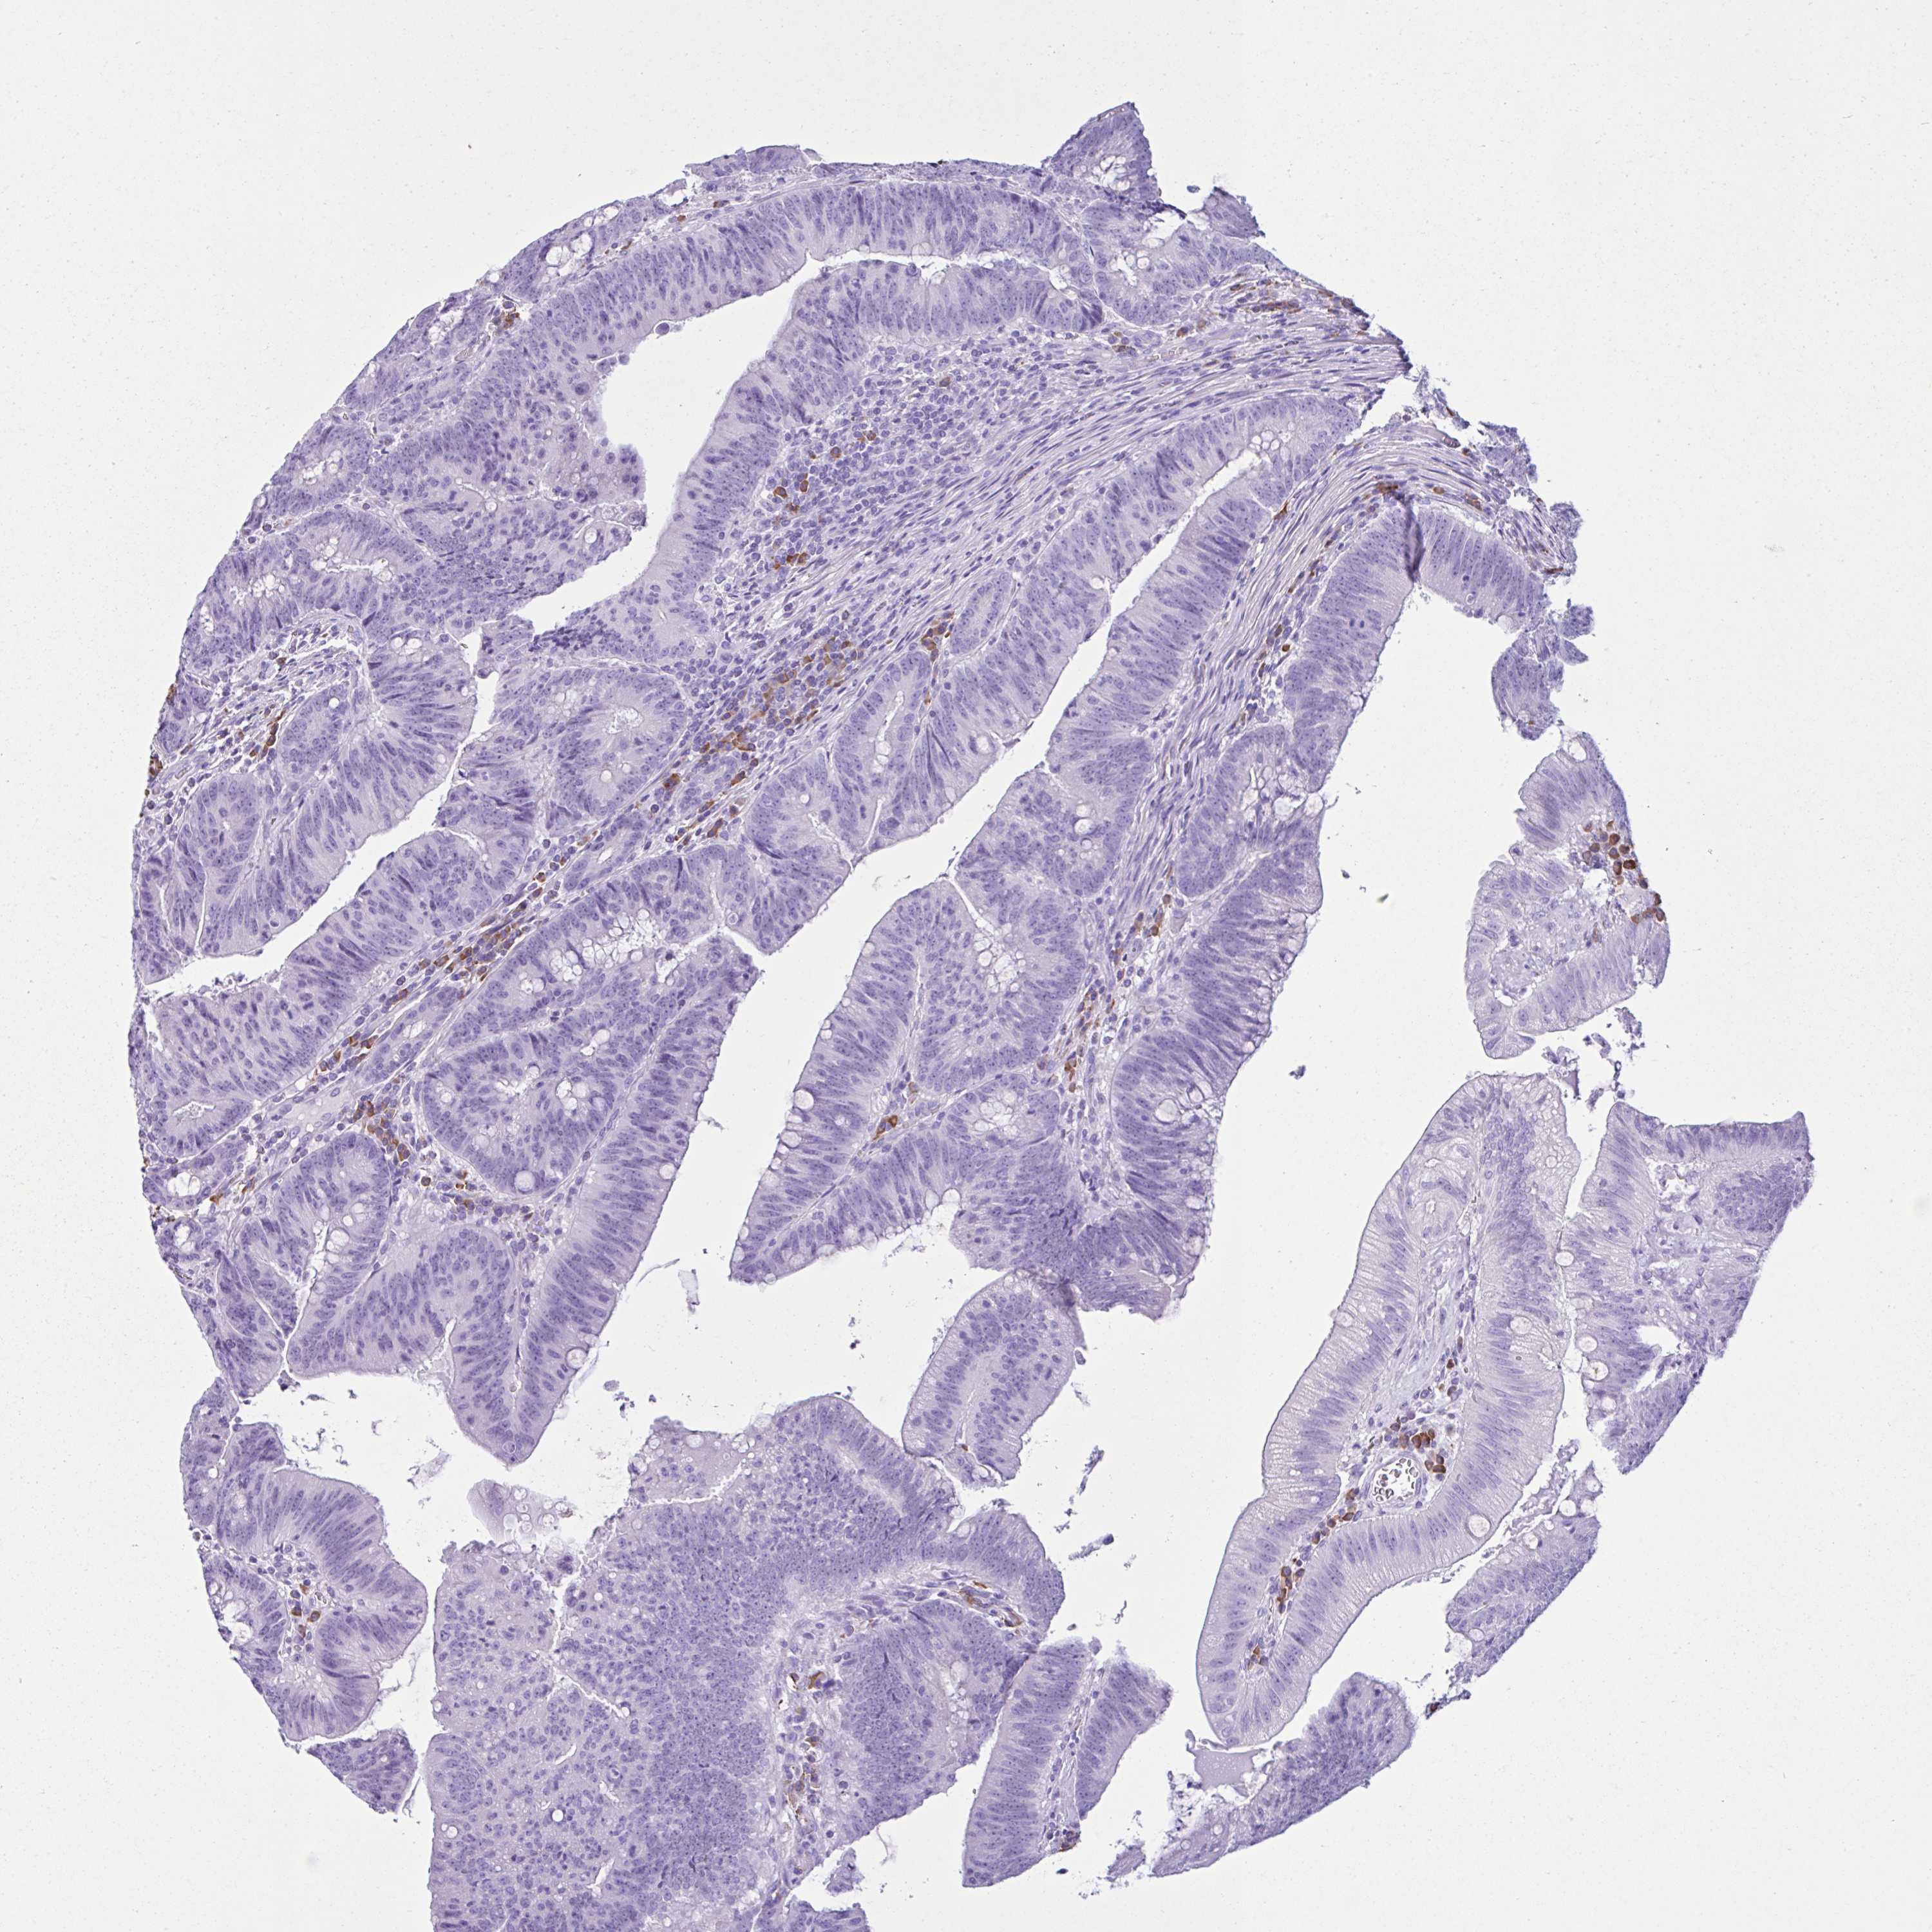

CANCER COLORECTAL CANCER Show tissue menu

Colorectal cancer

Human cancer

Colon adenocarcinoma

Rectum adenocarcinoma